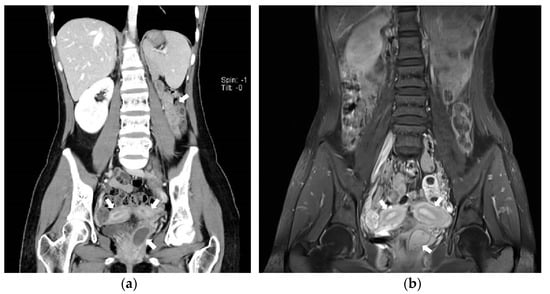

Figure 3. Abdominopelvic CT images. (a) Axial view showing the two uterine corpuses (indicated with white arrows); (b) Coronal view suggesting Herlyn-Werner-Wunderlich syndrome. White thick arrow; agenesis of right kidney. White thin arrow; hematocolpos of obstructed hemi-vagina connected with right endometrial cavity.

On the abdominopelvic CT image taken at the ER, we noticed she had HWW syndrome (right side hemi-vagina and right kidney agenesis) with acute pyelonephritis (APN) of the left kkidne (Figure 3a,b). After admission, transvaginal USG (Figure 4) and pelvic MRI (Figure 5a–c) were performed. We planned to perform the vaginal wall resection surgery on the next menstrual period as she needed antibiotics treatment for the APN, and the amount of hematocolpos was not so extensive that we could not clearly identify the bulging vaginal wall.